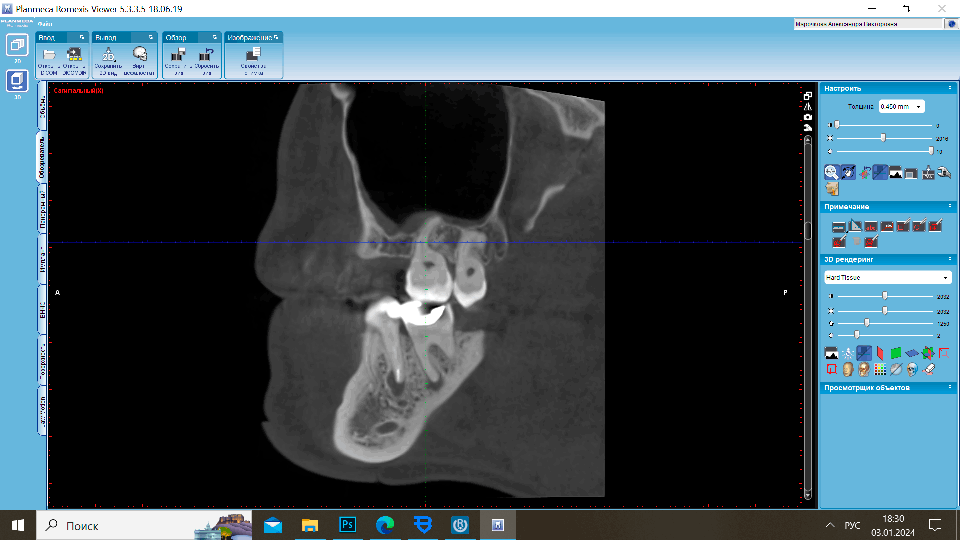

Диагностика кист зубов и других воспалительных процессов – ключевой этап в разработке эффективной стратегии лечения. В то время как обычные рентгеновские снимки предоставляют неполную информацию о наличии кисты,

Обычные рентгеновские снимки дают двумерное представление и могут ограничивать понимание структуры и объема повреждения костной ткани. В случае корневых кист, где важна оценка объема пораженной кости, КТ становится более эффективным инструментом. Трехмерные изображения, предоставляемые КТ, позволяют врачу полностью визуализировать проблему, определяя размеры, форму и расположение кисты.

Особенно важно отметить, что при установке коронок необходимо проверять наличие воспалительных процессов за верхушкой зуба. Компьютерная томография детально отображает анатомию корневых каналов, обеспечивая высокую детализацию, что значительно улучшает планирование эндодонтического лечения.

Понимание структуры и состояния корней зубов на глубоком уровне, предоставляемое КТ, является необходимым для успешного проведения эндодонтических процедур. Это позволяет разработать индивидуальный план лечения и обеспечить более высокие шансы на успешное преодоление корневых кист зубов.